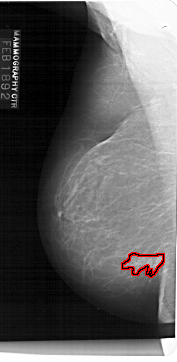

A_1132_1.LEFT_MLO

LEFT_MLO LINES 6871 PIXELS_PER_LINE 3346 BITS_PER_PIXEL 12 RESOLUTION 43.5 OVERLAY

FILE: A_1132_1.LEFT_MLO.OVERLAY

TOTAL_ABNORMALITIES 1

ABNORMALITY 1

LESION_TYPE MASS SHAPE IRREGULAR MARGINS ILL_DEFINED

ASSESSMENT 4

SUBTLETY 5

PATHOLOGY MALIGNANT

TOTAL_OUTLINES 1

BOUNDARY